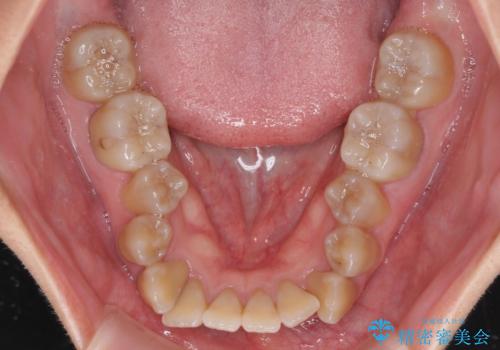

八重歯とクロスバイト 目立たないワイヤー装置での抜歯矯正

- 八重歯や前歯のデコボコを気にして来院された患者様です。

歯列が前方に傾斜しており、デコボコが強かったため、上下左右第一小臼歯4歯を抜去し、ワイヤー装置による矯正治療を行うこととしました。

上下の正中がずれていましたが、抜歯矯正であったので、極力正中位置を合わせるように治療を進めて行きました。

顎間ゴムの使用などにより、正中位置を改善することができました。